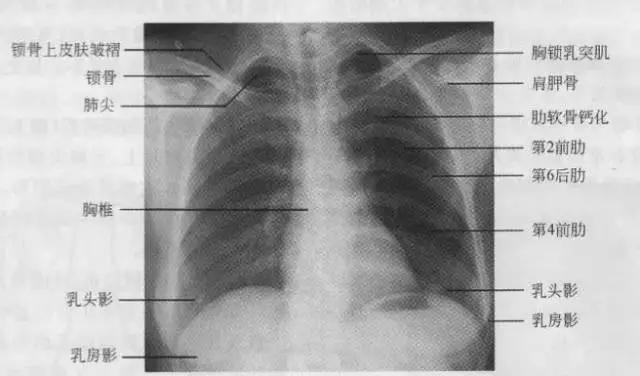

7、胸廓

正常胸廓由软策划与骨骼组成,两侧对称。

① 骨性结构: 肋骨、锁骨、肩胛骨、胸椎

② 软策划结构:胸锁乳头肌、锁骨上皮肤皱褶、胸大肌、女性乳房 / 乳头